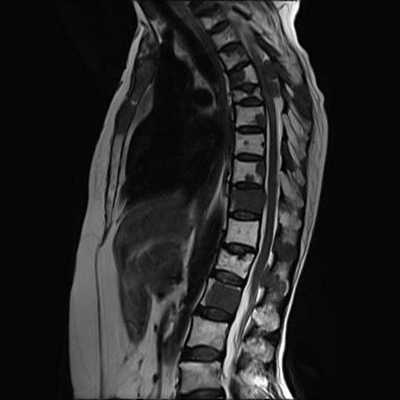

5. МРТ костного трансплантата позвоночника:

• Т1-ВИ:

о Костный пластический материал может выглядеть по-разному:

- Аутокостные трансплантаты могут характеризоваться усилением интенсивности Т1-сигнала, характерным для жирового костного мозга, или снижением интенсивности сигнала вследствие отека

- Аллотрансплантаты обычно характеризуются низким сигналом

• Т1-ВИ с КУ:

о Малоинформативны в свежих случаях, когда необходимо оценить положение трансплантата или выявить признаки эпидурального кровоизлияния, однако это исследование обязательно при подозрении на инфекционное осложнение

(Справа) Случай хирургического лечения ложного сустава и нестабильности (артропатия Шарко). Межтеловой спейсер сместился назад в спинномозговой канал. Обратите внимание на костный материал, использованный для заднего спондилодеза, и педикулярный винт в левом корне дуги. (Слева) Сагиттальный срез, Т2-ВИ: некорректное расположение межтелового спейсера на уровне L4-L5: задний край спейсера деформирует стенку дурального мешка и продолжается в зону, где проходит корешок L5.